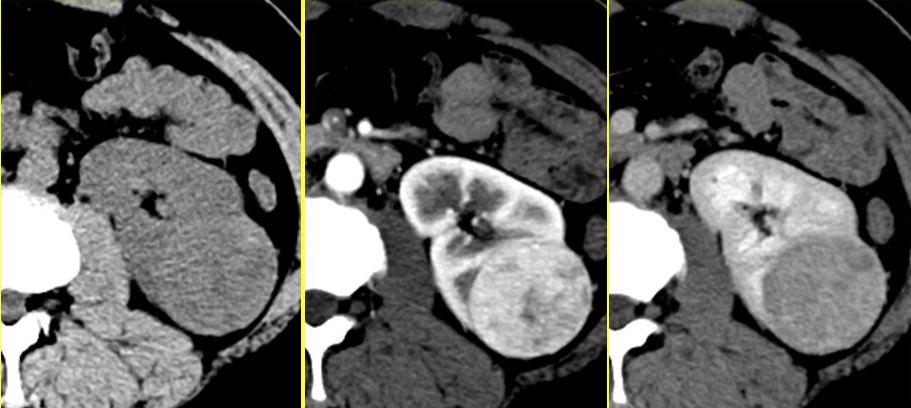

我们从医院拿回来的泌尿系CT片,通常有三组,一组上面的肾脏是灰色的,这是“平扫期”的片子;另外一组片子上面的肾脏边缘是白色的,这是“动脉期”,也叫“皮质期”。还有一组片子上面的肾脏内部是白色的,这是“实质期”,也叫“髓质期”。

? ? ? ? ? ? ? ? ? ? ? ? ? ? ? ? ? 平扫期? ? ? ? ? ? ? ? ? ? ? ? ? ? ? ? ? ? ? ? ? ? ? ? ? ? ? ?动脉期? ? ? ? ? ? ? ? ? ? ? ? ? ? ? ? ? ? ? ? ? ? ? ? ? ? ? ?实质期

由于泌尿系统疾病的特殊性,绝大多数医疗机构的泌尿系CT,往往还有第四组片子,即“排泄期”,

? ? ? ? ? ? ? ? ? ? ? ? 平扫期? ? ? ? ? ? ? ? ? ? ? ? ? ? ? ? ? ? ? ? 实质期? ?? ? ? ? ? ? ? ? ? ? ? ? ? ? ? ? ? ? ?动脉期? ? ? ? ? ? ? ? ? ? ? ? ? ? ? ? ? ? ? ? ? 排泄期